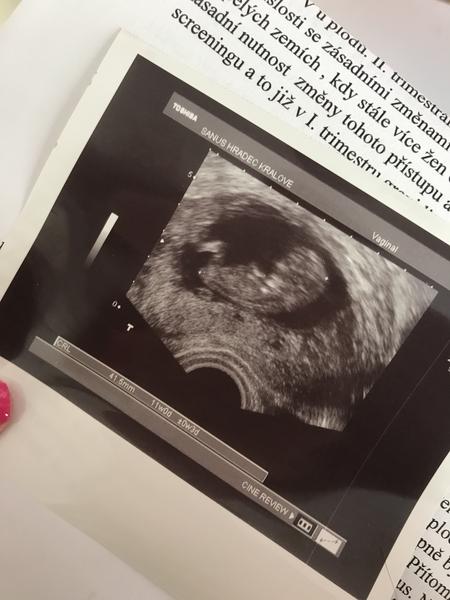

@luciebx já jsem v pátek večer zaspinila tak jsem pelasila na pohotovost. Tam mi prohlédl dr,udělal ultrazvuk a nabral hcg.Bylo mi řečeno, že se to stává. A vše ,, asi" v pořádku. Když jsem volala za 2h na výsledky hcg tak mi řekli že oproti tomu,co vidí na ultrazvuku je hcg strašně vysoké (17600) tak jsem musela v sobotu ráno zpátky na podrobnější vyšetření. Byl tam jiný dr, který mě vyšetřil a nic špatného neshledal. Dokonce jsem viděla i obě srdíčka ❤ (úplně poprvé). Zítra mám jít na kontrolu ale to špinění je pořád a pocit na MS také jsem z toho úplně vyplasena 😢 vůbec nevím, co si mám myslet... Hrozně se o ty mrnousky bojím.